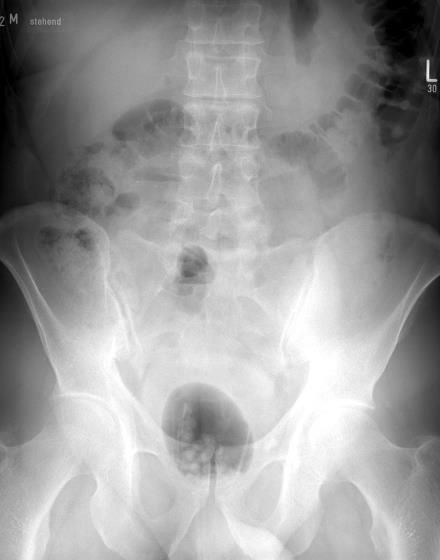

Gefährlicher ist, wenn Fremdkörper rektal appliziert werden: Dann besteht nämlich das Risiko, dass sie ins Rektum dislozieren und dort möglicherweise perforieren. Fremdkörper können sich relativ leicht im Rektum festsetzen. Grund: Viele der zur sexuellen Stimulation verwendeten Gegenstände sind an ihrer Spitze zwar konisch geformt, damit eine leichte Penetration gewährleistet ist. An ihrem Ende sind sie aber meist flach, sodass sie sich bei „Verlust“ im Enddarm gewissermaßen verhaken. Eine Perforation des Rektums ist eine lebensbedrohliche Komplikation, die eine sofortige meist offene Intervention erfordert. Kann eine Perforation ausgeschlossen werden, kann man versuchen, den Fremdkörper endoskopisch zu bergen.